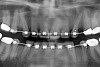

Figure 4a  Corticotomy SFOT. A 42-year-old male presented with a history of extraction orthodontic therapy (A). Incisors were too upright and had severe incisal wear. He was concerned about esthetics of the worn teeth and his insufficient lip support.

Figure 4a

Figure 4b  Progress photo and panorex 9 months after corticotomies were performed on Nos. 6 through 11 (B and C). Previous extraction sites were reopened orthodontically to improve function and fill lip support. Incisal edges were restored provisionally with composite resin. Note that despite the creation of adequate spaces to replace missing teeth, there is inadequate room for placement of dental implants because of severe tipping of all the anterior teeth. Osteotomy SFOT may have been a better choice because it would have allowed needed alveoloskeletal correction (without excessive tipping) instead of the primarily dentoalveolar correction common in corticotomy SFOT. Restorative dentist: Brad Jones, DDS.

Figure 4b

Figure 4c  Progress photo and panorex 9 months after corticotomies were performed on Nos. 6 through 11 (B and C). Previous extraction sites were reopened orthodontically to improve function and fill lip support. Incisal edges were restored provisionally with composite resin. Note that despite the creation of adequate spaces to replace missing teeth, there is inadequate room for placement of dental implants because of severe tipping of all the anterior teeth. Osteotomy SFOT may have been a better choice because it would have allowed needed alveoloskeletal correction (without excessive tipping) instead of the primarily dentoalveolar correction common in corticotomy SFOT. Restorative dentist: Brad Jones, DDS.

Figure 4c